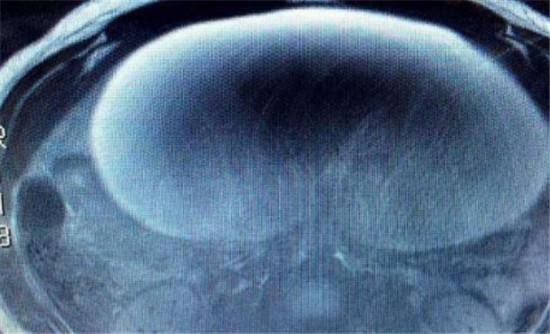

奥莉薇亚的肚子从两年前就开始渐渐大了起来,但是没有其他的感觉,于是她没有理会,一直到那天肚子痛才到医院就医。原来奥莉薇亚的卵巢中长了一个30公分大的囊肿。囊肿重达九公斤,很有可能会危及生命。

这么大的囊肿,医生立刻就安排手术,现在囊肿已经切除了,而且癌细胞没有扩散。奥莉薇亚知道真相之后才觉得后怕,自己的肚子里有一个气球随时爆炸,自己居然没有理会。现在她已经恢复健康,真是幸运。

虽然这颗肿瘤看起来很凶险,但是手术非常成功,没有危及奥莉薇亚的生育能力。